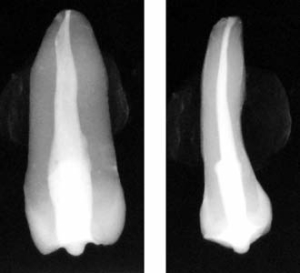

Figure 4--Radiograph of a bicuspid after obturation. Both plains are free of voids.